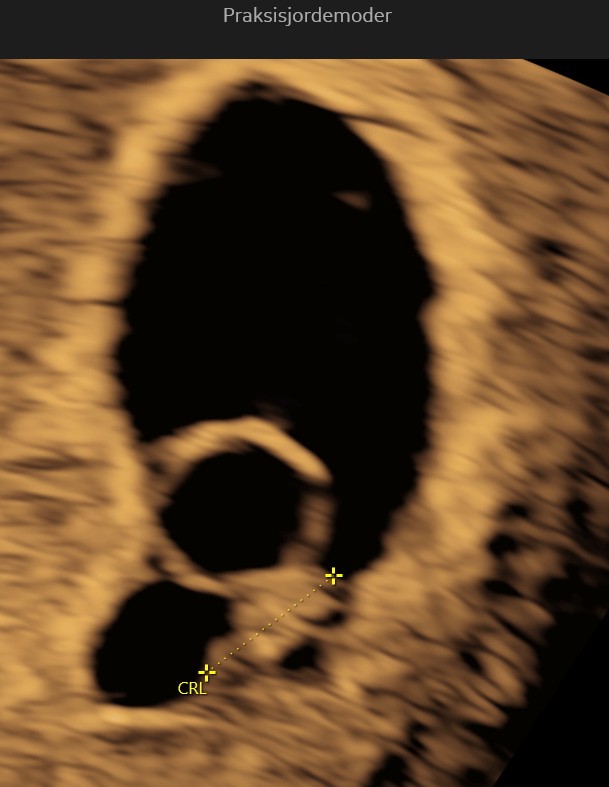

(6+0 til 6+6)

Embryoet er nu omkring 1 cm langt. Arm- og benknopper bliver tydeligere, og vigtige organer som lever og mave begynder at dannes. Navlestrengen fungerer nu og transporterer næring og affaldsstoffer mellem dig og barnet.

I uge 7 er din lille baby omkring 1,1 cm langt, omtrent på størrelse med et blåbær. Der sker mange vigtige udviklinger denne uge: